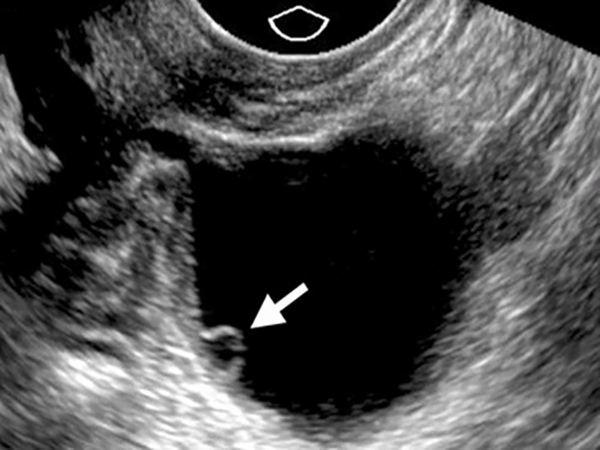

Theo chia sẻ từ bác sĩ Phạm Thị Ngọc Điệp, siêu âm canh trứng là phương pháp theo dõi sự phát triển của nang trứng bằng đầu dò hoặc siêu âm ổ bụng. Phương pháp này được thực hiện từ ngày thứ 9 đến ngày thứ 17 của chu kỳ kinh nguyệt.

Chu kỳ kinh nguyệt sẽ được chia ra thành 2 giai đoạn là giai đoạn nang và giai đoạn hoàng thể. Ở giai đoạn nang, trứng có kích thước ban đầu khoảng 4mm và phát triển đến 10 – 12mm ở ngày thứ 7 – 8 của chu kỳ kinh nguyệt. Đến giữa chu kỳ tức ngày thứ 14, nang trứng có thể đạt đến 18 – 20mm. Khi trứng đạt kích thước 20 – 28mm là lúc trứng đã sẵn sàng để rụng.

Việc siêu âm canh trứng giúp bác sĩ theo dõi và đo kích thước trứng để biết trứng đã trưởng thành hay chưa, chẩn đoán thời điểm trứng rụng. Khi xác định được khi nào trứng sẽ rụng sau khi siêu âm, bác sĩ sẽ tư vấn ngày giao hợp để tăng tỷ lệ thụ thai.

– Siêu âm canh trứng bằng đầu dò thực hiện qua ngã âm đạo, thường được chỉ định trong trường hợp nang trứng chưa trưởng thành, kích thước còn nhỏ. Siêu âm đầu dò cũng được sử dụng nhiều hơn bởi nó cho kết quả chính xác hơn, đồng thời quan sát được cả tử cung, buồng trứng.